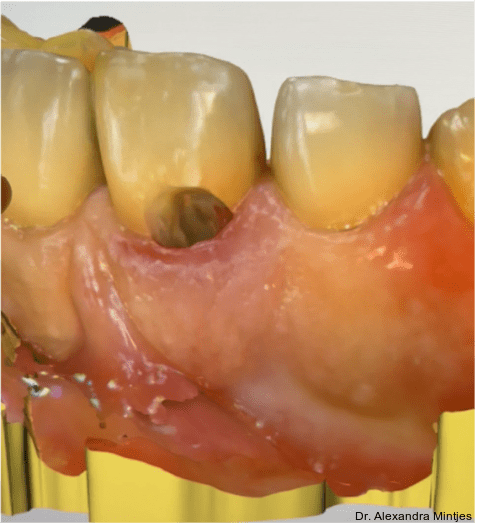

Die Sondierung ergab eine vertikale Defektausdehnung von etwa sechs Millimetern bei einer Taschensondierungstiefe von lediglich zwei Millimetern. Dies wies somit auf eine parodontale Gesundheit hin. Der gereinigte Defekt wurde anschließend mit einem lichthärtenden Flow-Komposit versiegelt, um Unebenheiten auszugleichen und die Adaptation der geplanten CEREC-­Keramikrestauration zu optimieren (Abb. 4).

Die Kavität wurde durch einen digitalen Scan abgeformt. Zusätzlich wurde eine Doppelmischabformung unter Verwendung von Alginat und Systoloid®-Hydrokolloid angefertigt, um eine spätere Anpassung der Restauration auf dem Gipsmodell durch die Zahntechnikerin zu ermöglichen (Abb. 5). Dabei spielte insbesondere der subgingivale Anteil eine entscheidende Rolle, da eine Anpassung in diesem Bereich direkt am Patienten eine erhebliche klinische Herausforderung darstellen würde. Danach wurde ein Schaumstoffpellet als temporärer Verschluss in die Kavität eingebracht, bevor ein provisorisches Onlay aus Telio® (Ivoclar) angefertigt wurde. Somit konnte eine retentive Formgebung und ein damit verbundenes Frakturrisiko bei der folgenden Entfernung des Provisoriums vermieden werden. Die Oberfläche des Provisoriums wurde bewusst rau gelassen, um eine möglichst einfache Entfernung zu gewährleisten.

Die Keramikrestauration wurde digital gestaltet und final auf dem Gipsmodell angepasst, um eine optimale Randadaptation zu erreichen (Abb. 6). Nach einer komplikationslosen Heilungsphase erfolgte die definitive ästhetische Versorgung. Die CAD/CAM-gefertigte Keramikrestauration aus Feldspat wurde eingesetzt und zur Optimierung der Randadaptation und Ästhetik mit einer Schicht Tetric EvoCeram® (Ivoclar) ergänzt (Abb. 7). Die adhäsive Befestigung erfolgte mit 3M™ RelyX™ Veneer in transluzenter Variante, um maximale Lichtdurchlässigkeit und eine harmonische Farbanpassung an die Nachbarzähne zu gewährleisten.